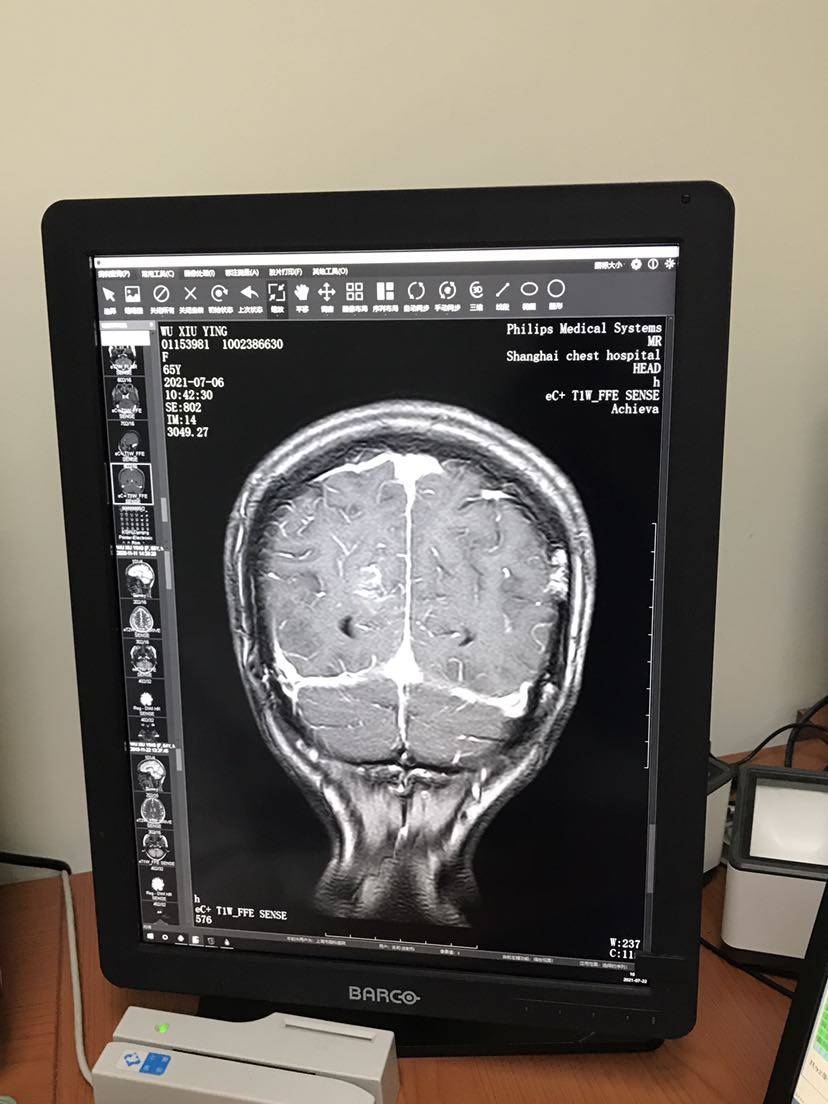

患者66岁,于19年4月右上肺叶切除,肺腺癌术后3a,21 l858r突变,19年6月开始易瑞沙至今,7月初复查结果身体各处指标和影像都正常,脑核磁显示右侧顶叶片絮状强化影,怀疑脑膜转移。

医生说影像和体感表现都不太像是脑膜转移,先继续易瑞沙两个月后复查。预约了下周神经科门诊还没到时间,所以想先问问大家的建议,万分感谢。